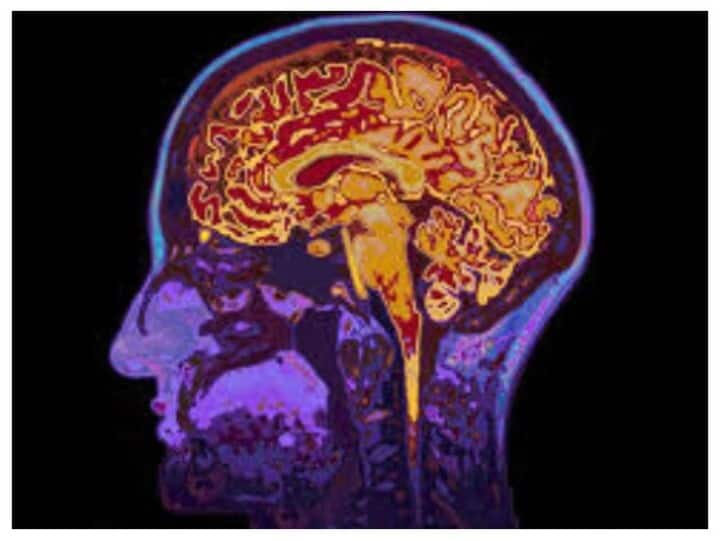

पेरिस यूनिवर्सिटी के रिसर्च में पता चला कि अनियंत्रित ग्लूकोज शुगर लेवल और दिमाग में इंसुलिन डिमेंशिया के विकास की दिशा में योगदान कर सकता है। पहले से ही डायबिटीज और वैस्कुलर डिमेंशिया, बीमारी की एक आम किस्म के बीच ज्ञात संबंध है। ऐसा इसलिए क्योंकि ये मस्तिष्क तक रक्त की आपूर्ति करने वाली वाहिकाओं को नुकसान पहुंचाती है और ऑक्सीजन के प्रवाह को रोकती है। फ्रांसीसी वैज्ञानिकों ने पाया कि 70 साल की उम्र में डिमेंशिया दोगुना हो जाता है अगर कोई में 10 साल पहले डायबिटीज की पहचान हुई हो।

उन्होंने बताया कि टाइप 2 डायबिटीज और डिमेंशिया के बीच चिह्नित संबंध का सटीक तंत्र स्पष्ट नहीं है। इसके अलावा रिसर्च डायबिटीज और अल्जाइमर की बीमारी का नमूना के बीच निरंतर संबंध हमेशा नहीं दिखाता है। वैज्ञानिकों ने संबंध का एक संभावित कारण यह बताया है कि मस्तिष्क तक इंसुलिन पहुंचता है। इसका मतलब हुआ कि ऊर्जा के लिए ग्लूकोज शुगर का इस्तेमाल करने में कम सक्षम है क्योंकि डायबिटीज के मरीजो की पर्याप्त मात्रा में पैदा नहीं करते हैं। दिमाग ग्लूकोज का इस्तेमाल अपने सामान्य तंत्र के काम को ऊर्जा देने और स्वस्थ कोशिकाओं को बहाल करने के लिए करता है, और उसकी कमी से अंग को नुकसान पहुंच सकता है।

शोधकर्ताओं ने बताया कि हाई ब्लड शुगर होने पर दिमाग बहुत ज्यादा ग्लूकोज अवशोषित करता है। बड़ी मात्रा में ग्लूकोज को जहरीला जाना जाता है और इन नसों और रक्त वाहिकाओं को भी नुकसान पहुंच सकता है। इसलिए डायबिटीज के मरीजों का पांव सुन्न हो सकता है। दिमाग की नसों या ब्लड आपूर्ति का नुकसान बढ़ सकता है जिससे डिमेंशिया होने का खतरा रहता है। रिसर्च के नतीजे को जर्नल ऑफ अमेरिकन मेडिकल एसोसिएशन में प्रकाशित किया गया है।